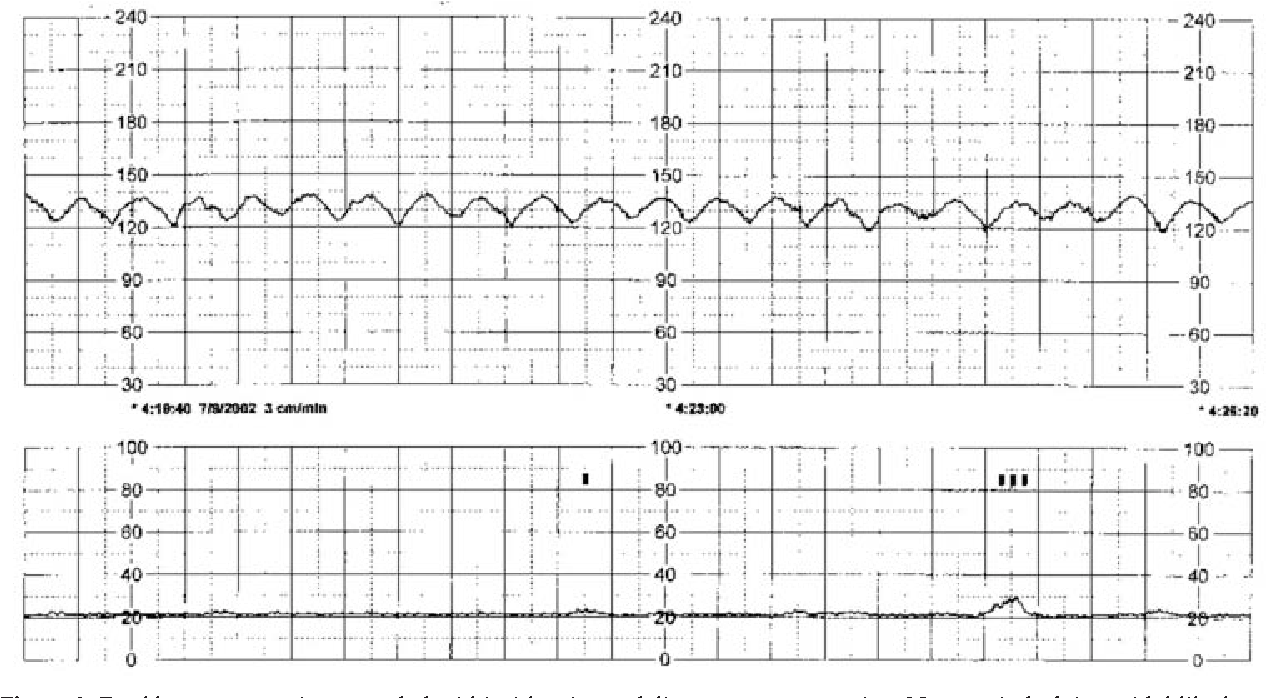

These patterns are characterized by a smooth, regular, and symmetrical waveform on the fetal heart rate monitor. They are different from the typical heart rate patterns seen during labor and delivery and may indicate certain underlying conditions.

Sinusoidal fetal heart rate patterns can be a cause for concern as they may be associated with fetal distress. It is important for healthcare providers to monitor these patterns closely and take appropriate action to ensure the well-being of both the mother and the baby.

There are various factors that can contribute to the development of sinusoidal fetal heart rate patterns, including fetal anemia, maternal bleeding, and certain medications. It is essential for healthcare providers to identify the underlying cause of these patterns and address it promptly.

If sinusoidal fetal heart rate patterns are detected during labor and delivery, healthcare providers may recommend additional tests and interventions to assess the baby’s well-being and ensure a safe delivery. Close monitoring and timely intervention can help prevent complications and improve outcomes for both the mother and the baby.

Figure 2 From Title Sinusoidal Heart Rate Pattern Reappraisal Of Its Definition And Clinical Significance Semantic Scholar